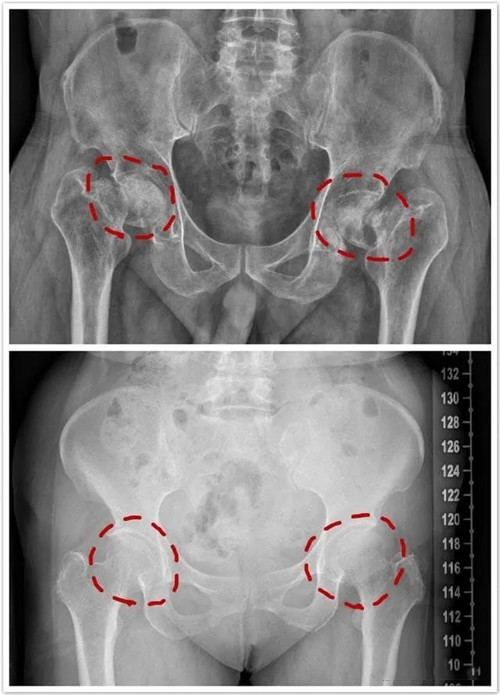

股骨头坏死人工关节置换术前及术后X线片

股骨头坏死是一种常见的髋关节疾病,其股骨头供血中断或受损,引起骨细胞及骨髓成分死亡及随后的修复,继而导致股骨头结构改变、股骨头塌陷、关节功能障碍等疾病。股骨头坏死患者年龄多集中于30~50岁,并且随着年龄增长,病发率呈现逐步递增的趋势。长期酗酒、气压剧烈变化、过量使用激素均可诱发股骨头坏死。大多数股骨头坏死患者早期无明显体征表现,当向患处施加重压时,受影响的关节才会出现疼痛感。随着病程发展,疼痛感会持续增强,患者即使患肢不活动,也会感到疼痛,并严重影响患肢的正常活动。